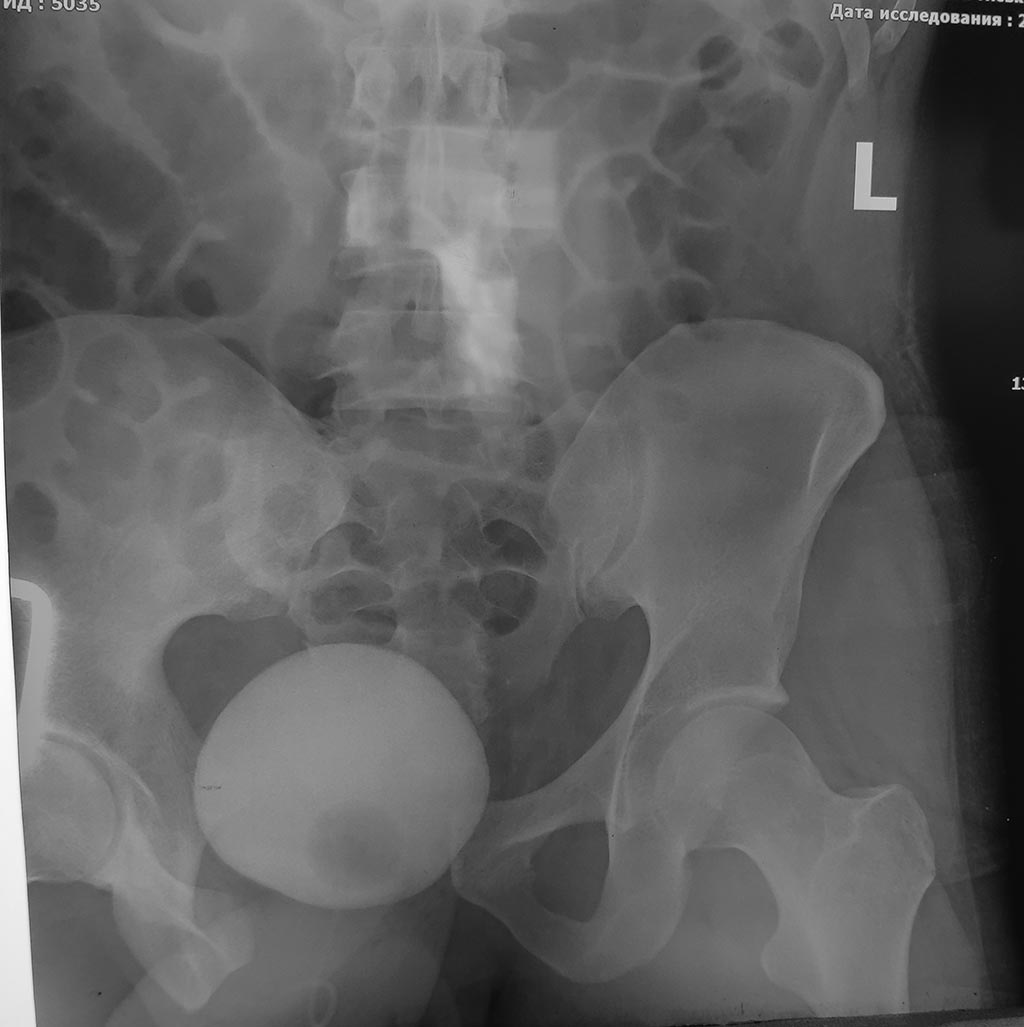

Повреждение таза после ДТП

такая вот травма таза при ДТП, интересно что при таком расхождении лона

мочевой пузырь остался целым